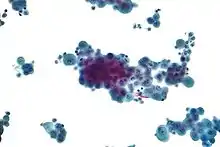

Micrograph of a pleural fluid cytopathology specimen showing malignant mesothelioma, one cause of a pleural effusion.

- If cancer is suspected, the pleural fluid is sent for cytology. If cytology is negative, and cancer is still suspected, either a thoracoscopy, or needle biopsy[5] of the pleura may be performed.